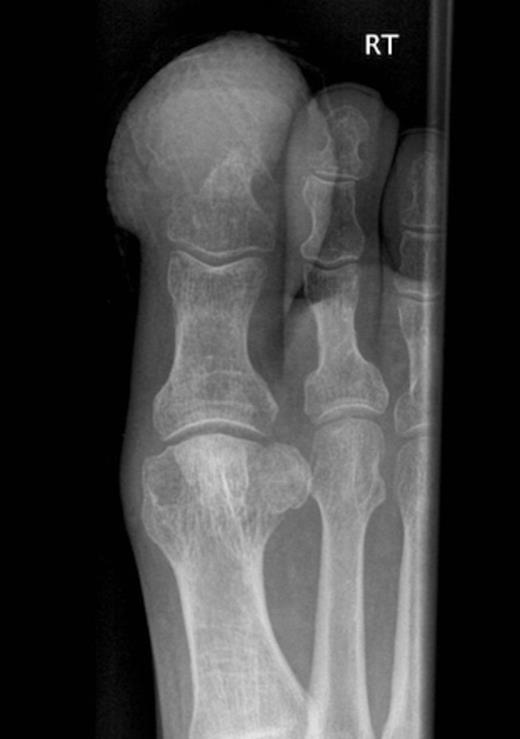

A chest radiograph demonstrated consolidation in the right lower zone. X-ray of the right great toe (Fig. 2) showed destruction of the distal phalanx with adjacent soft tissue swelling, and of the right elbow showed soft tissue swelling over the lateral aspect with possible cortical destruction of the lateral epicondyle (Fig. 3).

Radiograph of right great toe demonstrating osteolysis of distal phalanx with adjacent soft tissue swelling but no periosteal reaction.